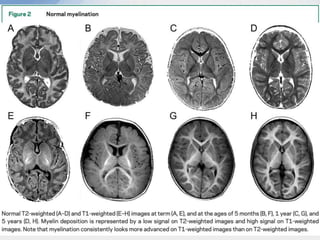

• The first myelination is seen as early as the 16th week of gestation, but only

really starts from the 24th week.

• It does not reach maturity until 2 years . It correlates very closely to

developmental milestones .

• The progression of myelination is predictable and abides by a few simple

general rules; myelination progresses from:

1. central to peripheral

2. caudal to rostral

3. dorsal to ventral

4. sensory then motor

Barkovich AJ, Kjos BO, Jackson DE, Norman D. Normal maturation of the neonatal and infant brain: MR imaging

at 1.5 T. Radiology 1988

Normal myelination